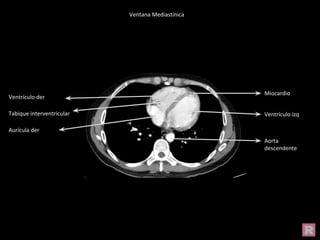

Miocardio

Ventrículo izq

Aorta

descendente

Ventrículo der

Aurícula der

Tabique interventricular